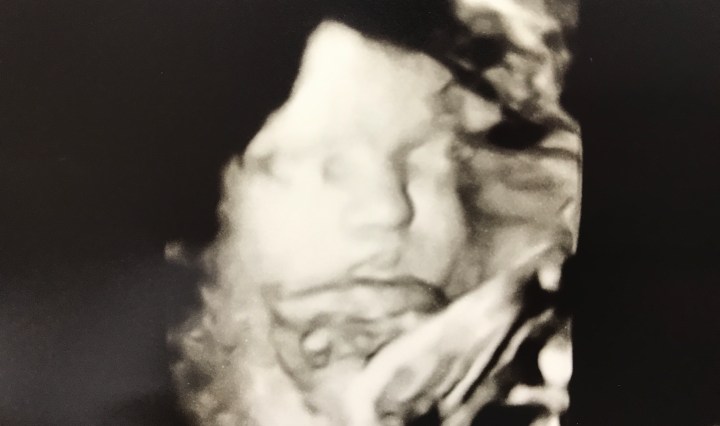

THIRD TRIMESTER

November 8, 2017February 20, 2020 Katlin Lindsey Chappell

“For you formed my inward parts, you knitted me together in my mother’s womb. I praise you, for I am fearfully and wonderfully made. Wonderful are your works; for my soul knows it very well.” Psalms 139:13-14 Continue reading THIRD TRIMESTER